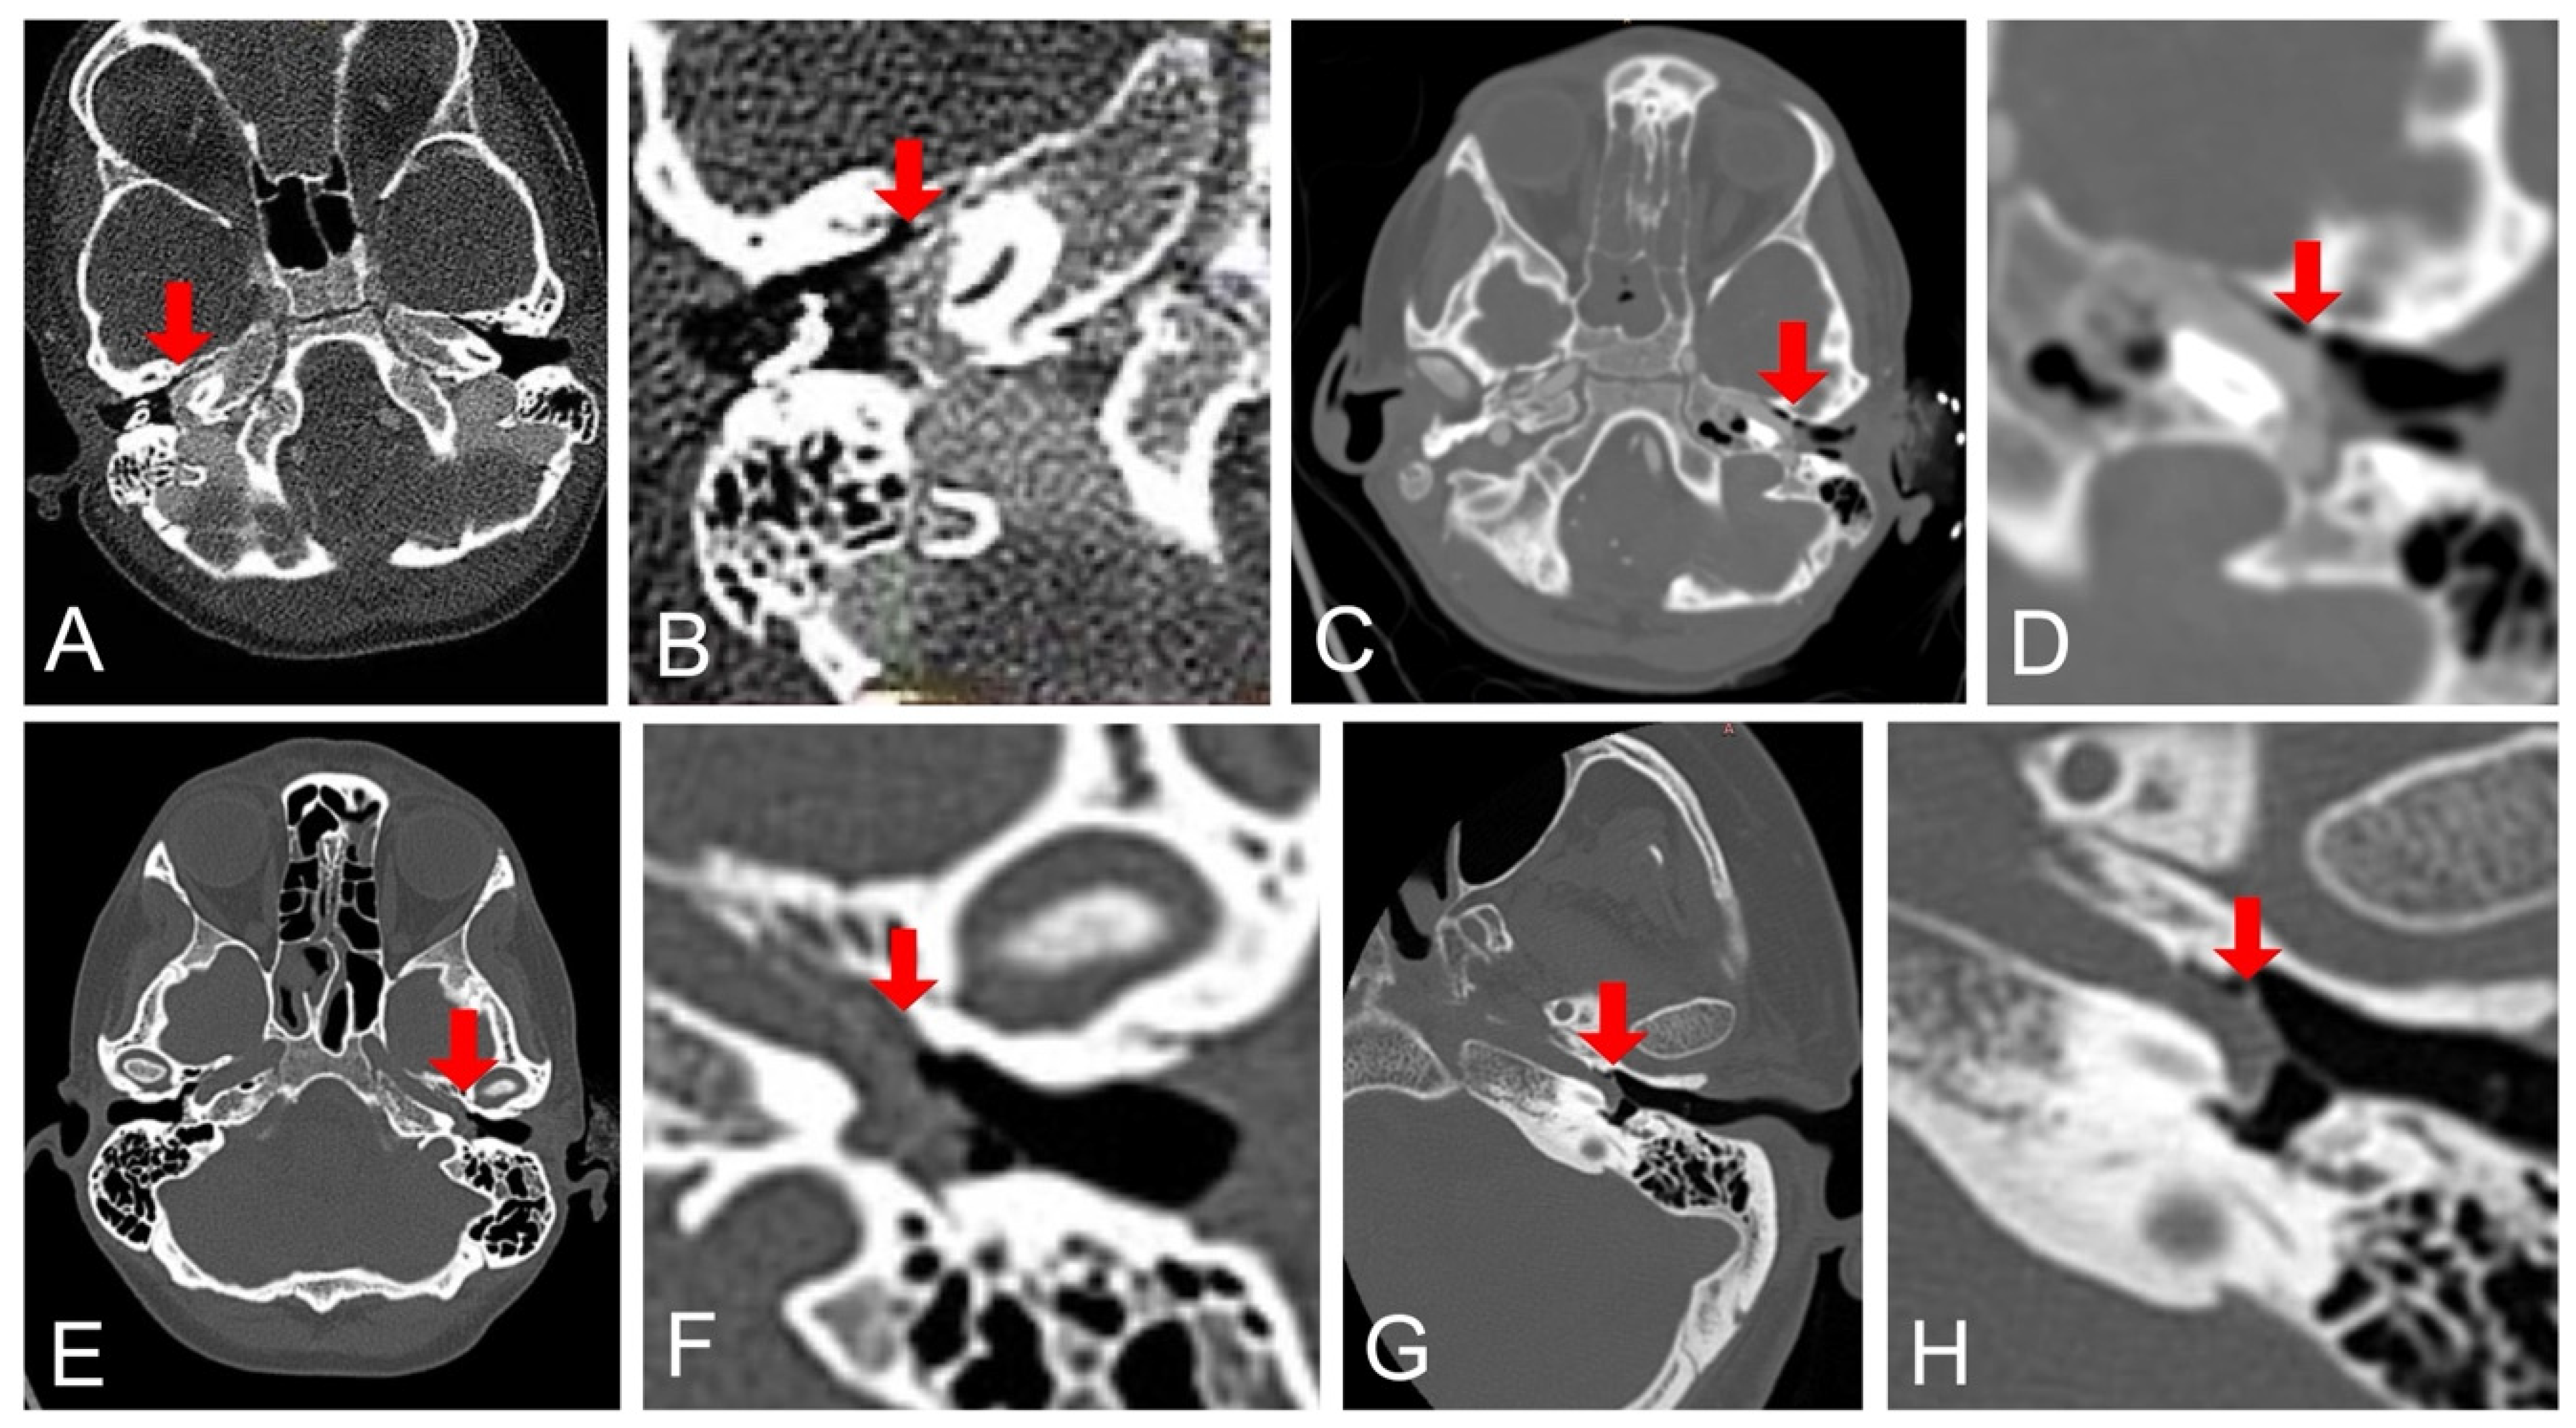

Figure 1. Axial CT temporal bone imaging. Overview and close-up of the tympanic cavity of case 1 (A,B), case 2 (C,D), case 3 (E,F), and case 4 (G,H), respectively. All aICAs, each with a similar course through the tympanic cavity in a dorsal to anteromedial direction, lateral to the cochlea in front of the promontory, are marked with a red arrow.

A 4.5-year-old boy underwent elective bilateral myringotomy and adenoidectomy for chronic otitis media with effusion and adenoid hypertrophy. Preoperative otoscopy revealed a thickened tympanic membrane on both sides but no other pathological findings. During surgery at an external outpatient facility, profuse acute bleeding occurred from the middle ear. Hemostasis was temporarily achieved with external auditory canal (EAC) packing, and the patient was transferred by air to a tertiary care center while intubated. His hemoglobin level dropped to 8.8 g/dL. Emergency CT angiography identified an aICA coursing through the right middle ear (Figure 1A,B), and he was admitted to the intensive care unit (ICU) for monitoring. Follow-up magnetic resonance (MR) angiography confirmed cessation of bleeding, allowing for the removal of the ear canal packing after two days.

During myringotomy, profuse arterial bleeding occurred from the left middle ear. Manual compression and EAC packing achieved initial hemostasis. Subsequent CT angiography identified an aICA running through the left middle ear as the source of bleeding (Figure 1C,D). Because of the high risk of re-bleeding and the presence of a large anterior communicating artery segment suggestive of good collateral circulation, a balloon test occlusion was not performed. Immediate coil embolization of the left ICA from the distal petrous to the distal cervical section was conducted via a right femoral access (Figure 3). A highly compliant dual lumen balloon (Scepter CS 4 × 11 mm, Terumo Neuro) was used to achieve flow arrest and to avoid coil migration during the procedure [23]. Post-procedure, he remained stable, with no post-procedural focal neurological deficit after extubation on the same day. On the third postoperative day, the ear packing was removed without complications.

A 39-year-old woman was referred to a tertiary ENT center from an outpatient clinic after severe bleeding from the left middle ear during needle puncture of the tympanic membrane for acute otitis media. She complained of pain, feeling of fullness and hearing loss “like underwater” in the left ear for 3 days. Her medical history included lymphocytic leukemia, allogeneic hematopoietic stem cell transplantation, and regular cyclosporine use. At the emergency department, the external dressing was removed to reveal the left EAC filled with blood clots but no ongoing hemorrhage. CT with contrast agent revealed an aICA in the left temporal bone located just below the promontory and minor blood accumulation in the left middle ear (Figure 1E,F). Neurological consultation stated no deficits. The blood hemoglobin was decreased (10.3 g/dL). Due to the lack of active bleeding after admission to the emergency department, the treatment was exclusively conservative and included EAC packing and pharmacotherapy with tranexamic acid. Despite the recommendation for inpatient monitoring, the patient declined admission and was discharged after a 5 h observation. An oral antibiotic with amoxicillin and clavulanic acid, cyclonamin, tranexamic acid, nasal steroid, and constriction drops were recommended. During over two years of follow-up, there was no recurrence of bleeding. The tympanic membrane healed within weeks, although it became noticeably thinner at the puncture site. Pure tone audiometry performed 3 months after the bleeding showed normal hearing in the left ear in the range of 125 Hz to 4 kHz, with a deterioration to 40 dB at 6 kHz and 70 dB at 8 kHz.

On the first day after the procedure, the patient developed confusion and aphasia. Contrast-enhanced CT scans and neurologic consultation confirmed an ischemic stroke in the left cerebral hemisphere with global aphasia and severe right hemiparesis. Angio-CT demonstrated an aICA through the left tympanic cavity in the promontory area with hypoplasia proximal to the tympanic segment, as well as complete occlusion for 25 mm before entering the internal carotid artery canal and in the intracranial section along its entire length (Figure 4). A 12-year-old CT scan, found retrospectively, had also shown the aICA (Figure 1G,H).